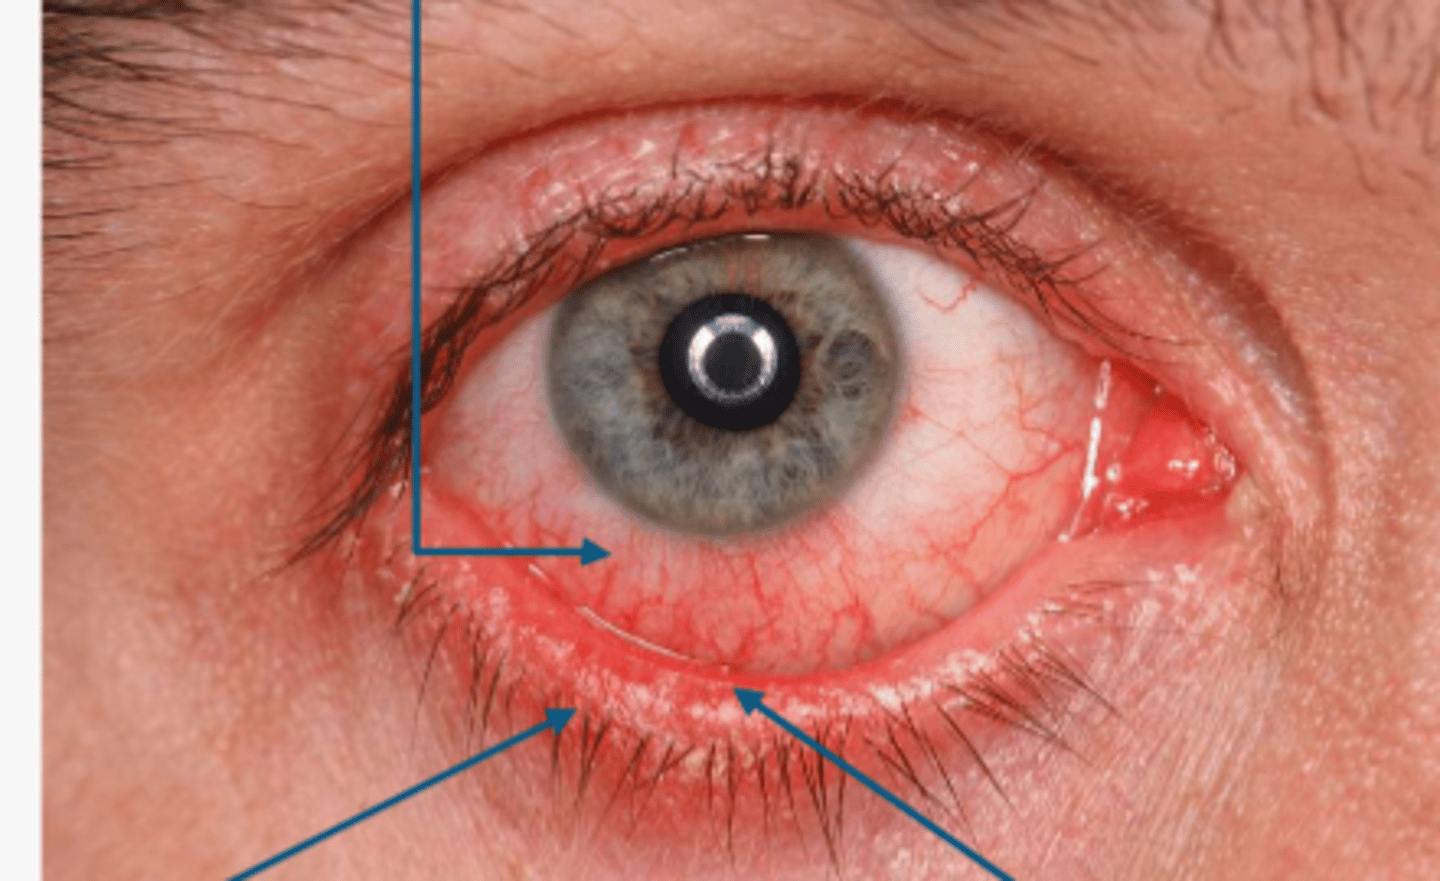

in hyperacute conjunctivitis, the presentation is

1. diffuse conjunctival hyperemia & chemosis

2.purulent discharge which is made of pathogen, wbc, dead cells

clinical signs for hyperacute conjunctivitis includes (7)

1. severe purulent discharge

2. + PA node

3. papillae

4. severe lid edema

5. SPK/erosions

6. infiltrates

7. risk for rapid corneal ulceration which lead to perforation

___ ___ ___ presents with beefy red injection (bacterial) and its greater on the palpebral and peripheral bulbar conj as well as scant discharge that can be purulent or mucopurulent